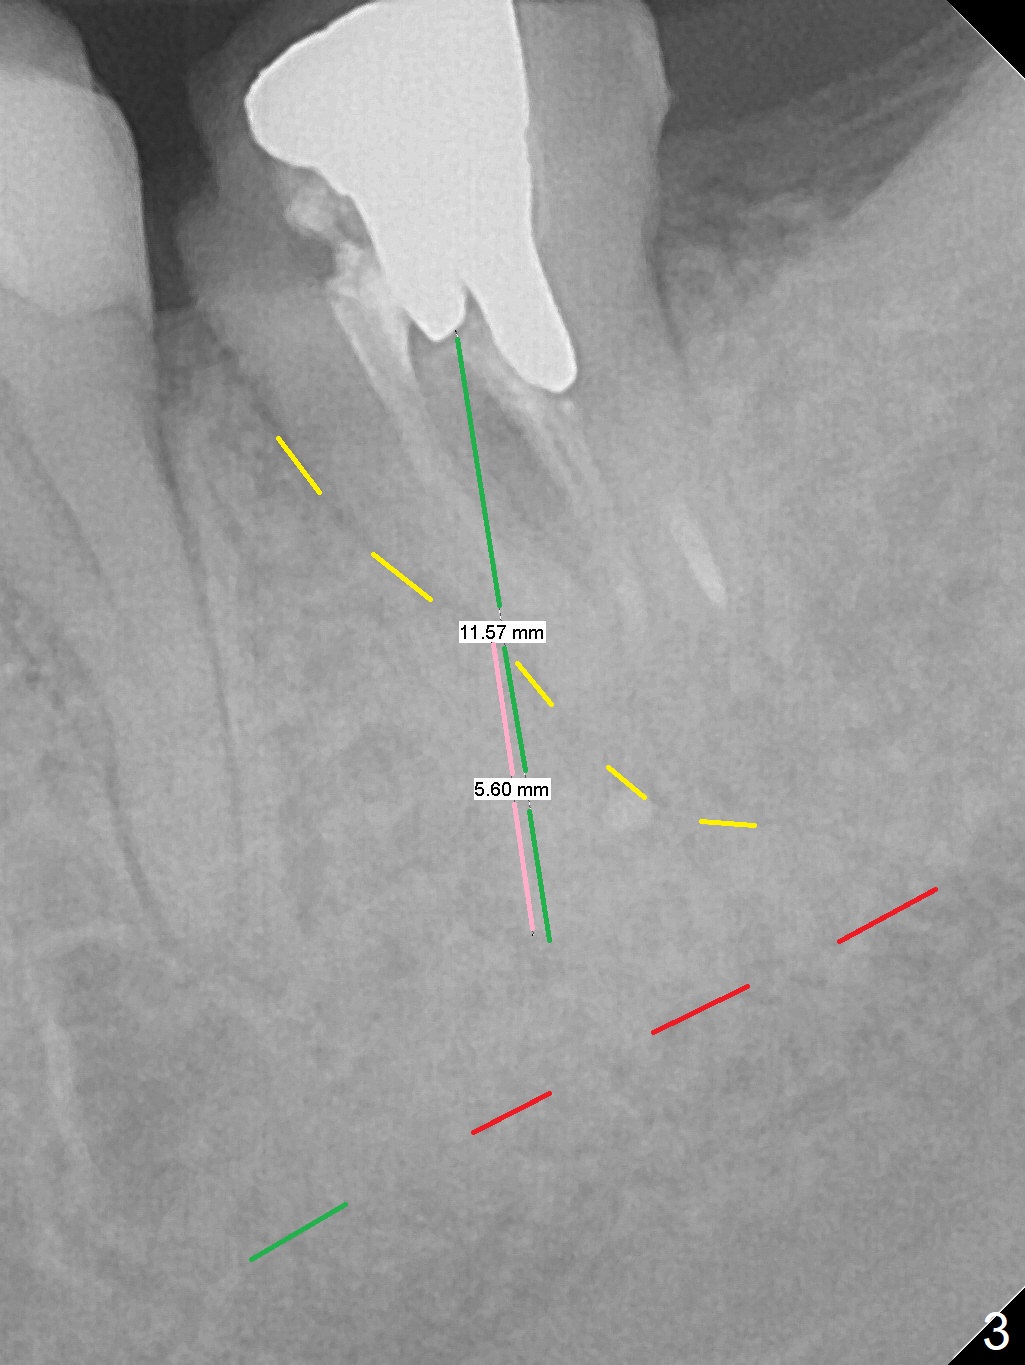

A 34-year-old woman has been our patient for >5 years. Since then, the teeth #17 and 32 have been extracted (Fig.1 x). The main issue is the metal crown at #18, which had occlusal perforation. The crown was recemented once. The mesiolingual margin is wide and subgingival. After redo, the Zirconia crown fractured once and finally dislodged (Fig.3), partially due to #15 supraeruption (Fig.2 arrow, trimmed during crown redo). Following extraction, use starter drill and 2 mm drill with 8 mm stopper to initiate osteotomy in the mesial slope of the socket (Fig.3 yellow line). The stopper should stop prematurely in the mesiocoronal aspect of the mesial slope, the depth should be a little longer than 5.6 mm (Fig.3 pink line). Insert a marked parallel pin for X-ray depth confirmation. Considering the opposing tooth supraeruption, a probably 5x10 mm SM implant will be placed deep with a cemented abutment with 1 mm cuff. But at first a temporary abutment will be used most likely. Make a provisional as wide as possible apically so that it is easy to take impression later on.